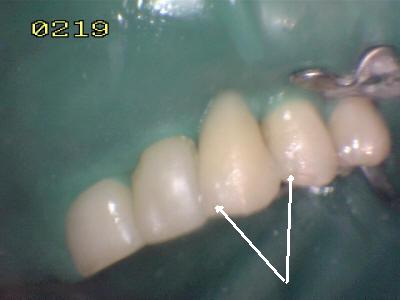

Procedimiento de cementado, se debe tener cuidado de eliminar los excesos de cemento (flechas blancas) antes de su endurecimiento; dado que el espesor de cemento puede ser importante por la desadaptación por caries.